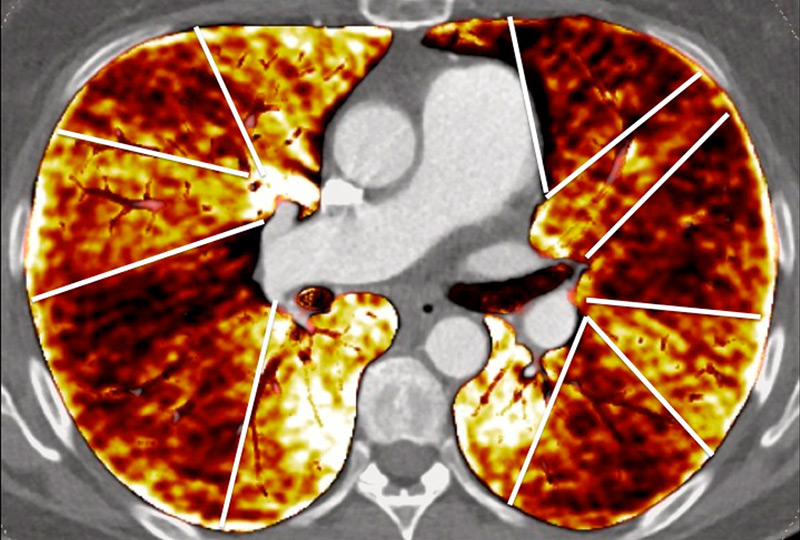

Figure 6

Perfusion heterogeneities in idiopathic pulmonary artery hypertension (stars) in two different patients (A/B). The dilatation of the arteries in pulmonary hypertension (arrows) is not always observed depending on the severity of pulmonary hypertension.